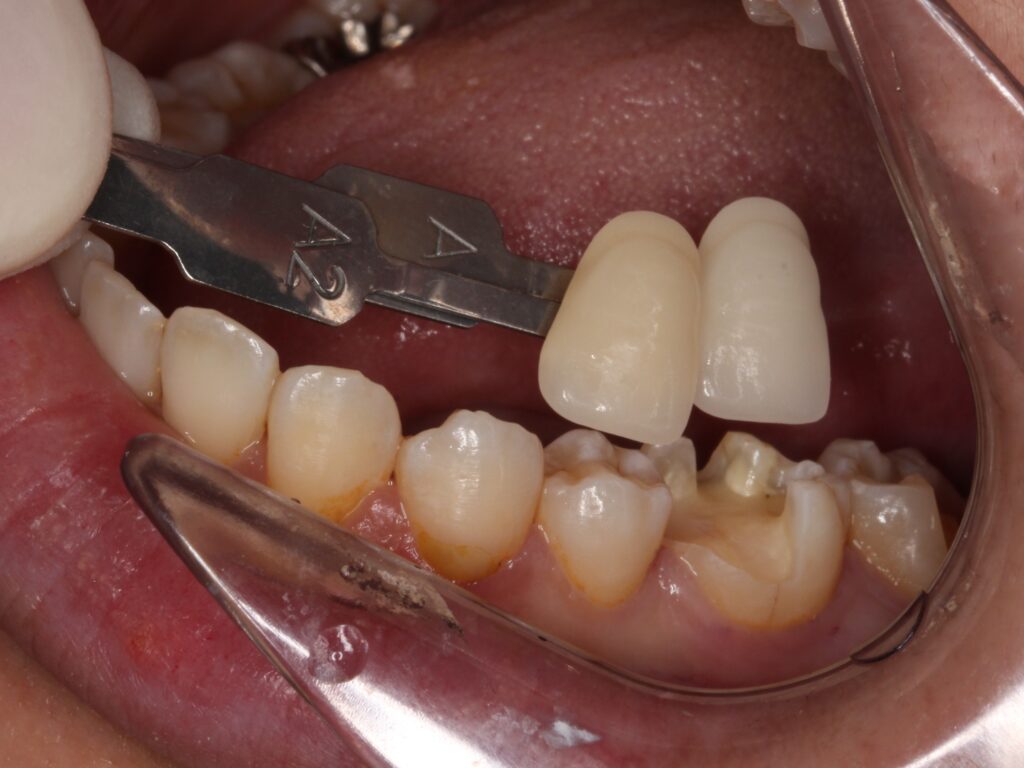

セラミックをセットして治療終了

歯の色を記録してセラミックを製作します。

ひとりひとり歯の色は違うため、歯の色を合わせて、

その方に合うセラミックを製作します。

後日、セラミックがセットされた状態です。

綺麗にセラミックが入りました(^^)/

どこを治療したか分からないくらいですね!